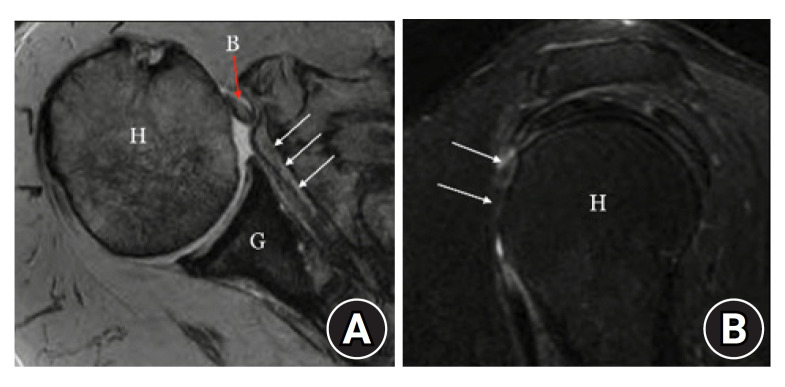

肩胛下肌撕裂无法修复导致的盂肱关节前部不稳定是肩部整形外科医生面临的一个难题。目前的技术(包括肌腱转移)效果不稳定,复发性不稳定的发生率很高。细胞真皮同种异体移植已被用于肩袖上部大面积撕裂的年轻患者,并取得了早期成功,但细胞真皮同种异体移植在前部缺损方面的研究相对较少。我们介绍了两例使用无细胞真皮同种异体材料重建前囊的病例,患者年龄分别为 66 岁和 58 岁,肩胛下肌腱撕裂无法修复。这两名患者的随访时间都超过了 4 年,前屈超过 140°,外旋超过 60°,单次数字评估得分超过 90 分,视觉模拟评分 0 分,美国肩肘评分 98 分。总之,无细胞真皮同种异体移植可用于重建肩胛下肌大面积不可修复撕裂患者的前囊,这与它在肩袖后上方大面积撕裂患者上囊重建中的应用类似。

Anterior glenohumeral instability with an irreparable subscapularis tear is a challenging problem for the orthopedic shoulder surgeon. Current techniques, including tendon transfers, yield inconsistent results with high rates of recurrent instability. Acellular dermal allografting has been used in young patients with massive superior rotator cuff tears with early success, but acellular dermal allografting is comparatively unstudied in anterior deficiency. We present two cases of anterior capsular reconstruction with an acellular dermal allograft in patients ages 66 and 58 years with irreparable subscapularis tendon tears. Follow-up for both patients exceeded 4 years, with forward flexion >140°, external rotation exceeding 60°, a Single Assessment Numeric Evaluation score >90 points, a visual analog scale score of 0 points, and an American Shoulder and Elbow Score of 98 points. In conclusion, acellular dermal allografting can be used to reconstruct the anterior capsule in patients with massive irreparable subscapularis tears, similar to its use in superior capsular reconstruction in patients with massive posterosuperior rotator cuff tears.